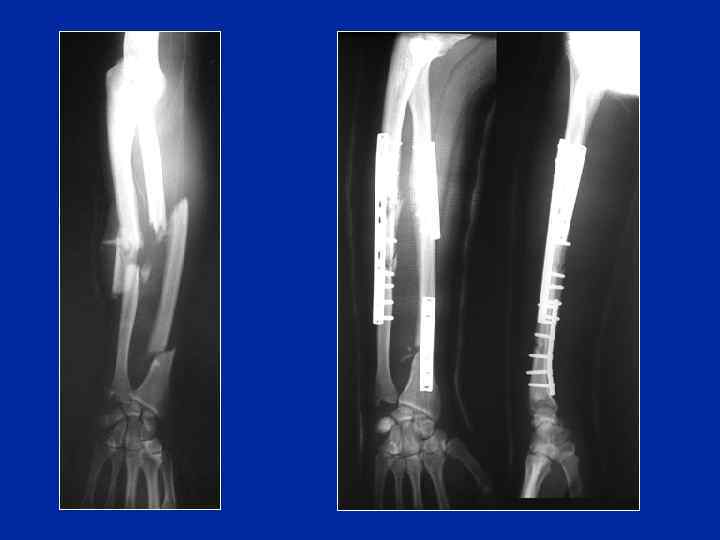

Fracture De L'avant Bras. Découvrez le traitement chirurgical et le temps de guérison

Découvrez le traitement chirurgical et le temps de guérison